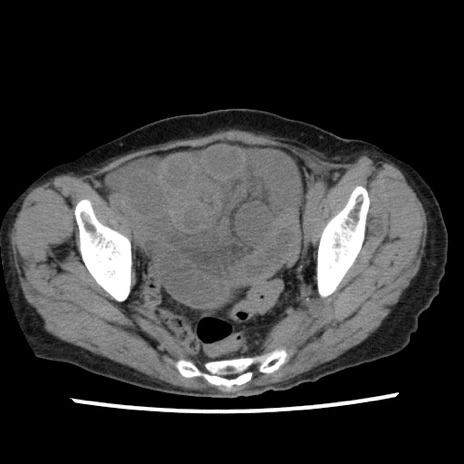

症例1(横断像)

【症例】80歳代女性

【主訴】腹痛

【現病歴】8時間前から腹痛あり来院。

【既往歴】糖尿病、脂質異常症、子宮体癌にて子宮全摘術

【身体所見】意識清明・会話良好だが腹痛で苦悶様、全腹部にわたって反跳痛と圧痛あり

【データ】WBC 13600、CRP 0.14、LDH 224、CK 90